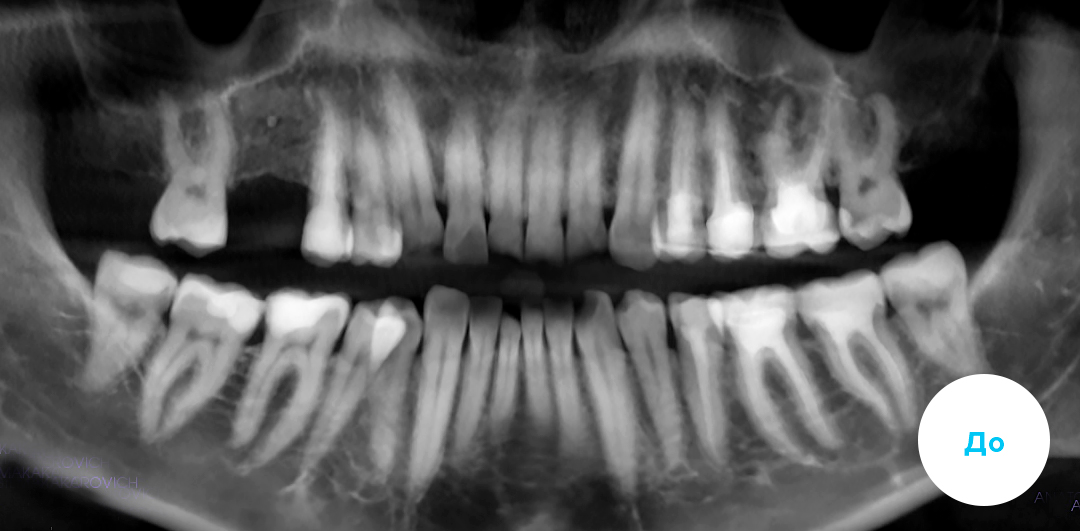

Лечение скученности с последующим протезированием.

Помимо ортодонтии проведено комплексное лечение. Установлен имплантат справа на верхней челюсти. Также пациенту требовался большой объем терапевтического лечения, чтобы привести зубы в порядок.

Пациенту 45 лет

Срок лечения: 21 мес